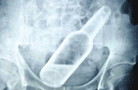

长沙男子被追债人从肛门塞入玻璃瓶(图)